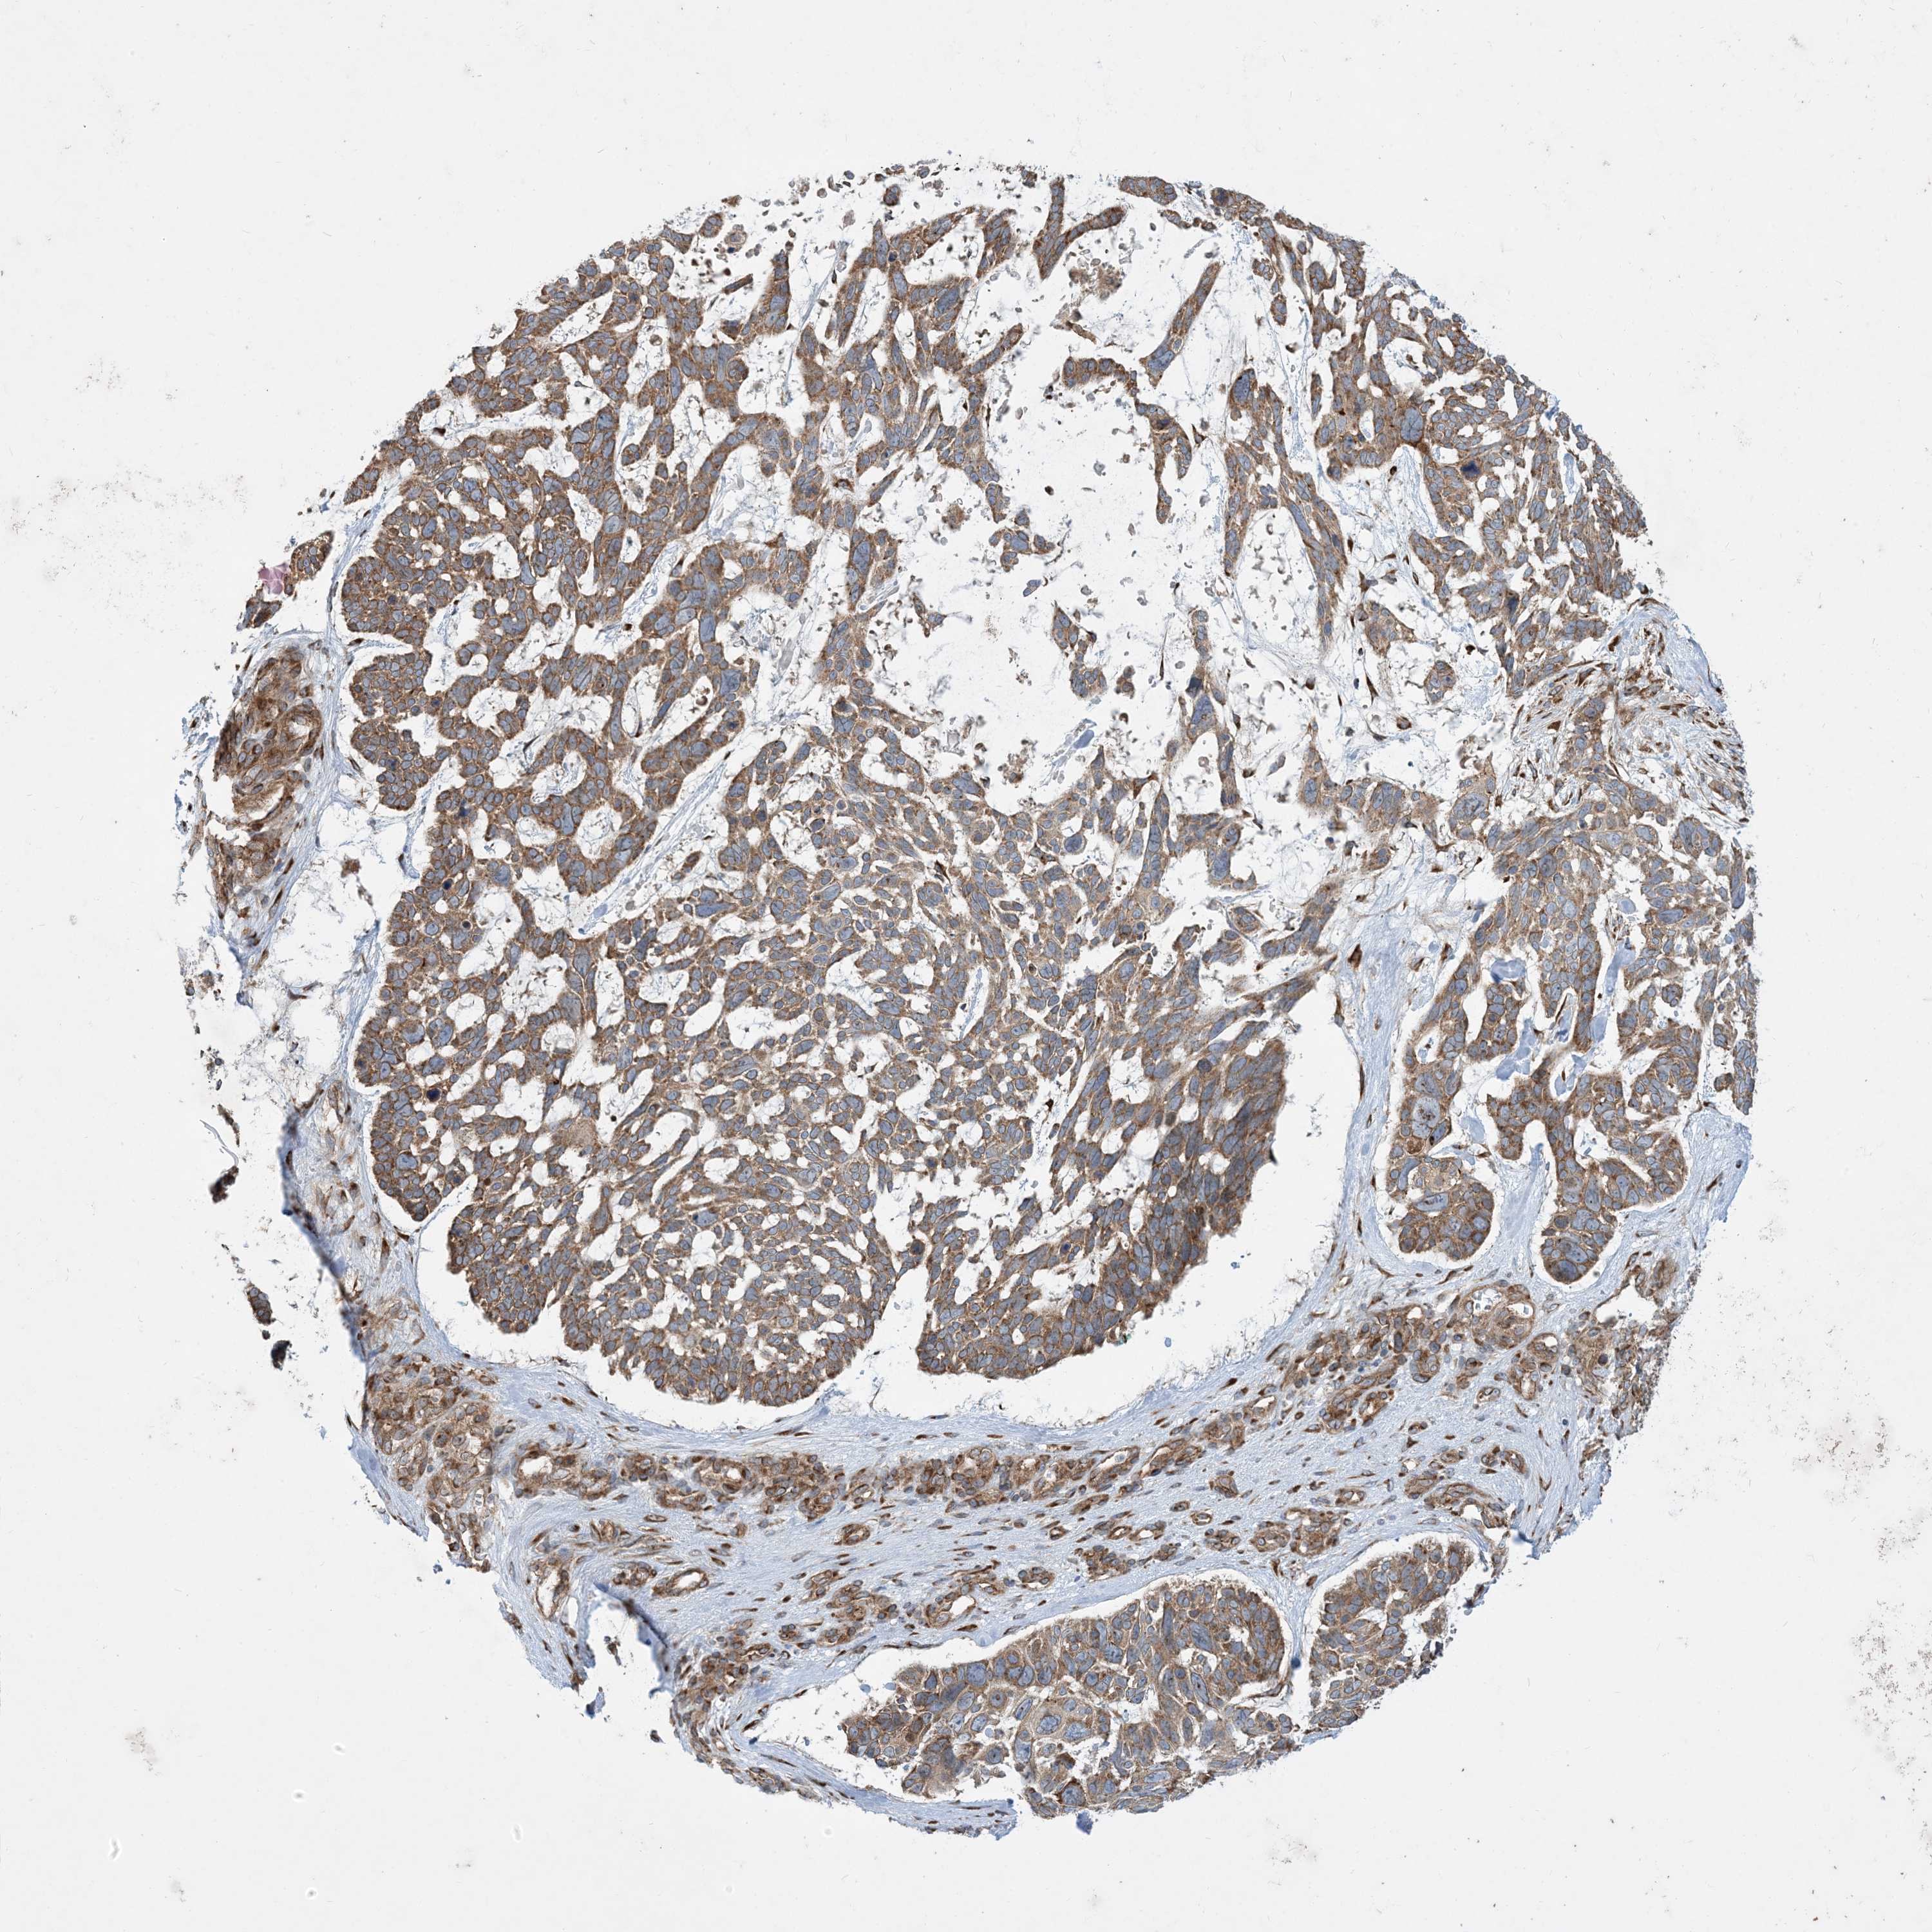

Basal cell and squamous cell cancer

SKIN CANCER - Protein expressioni

A mouse-over function shows sample information and annotation data. Click on an image to view it in a full screen mode. Samples can be filtered based on level of antibody staining by selecting one or several of the following categories: high, medium, low and not detected. The assay and annotation is described here.

Antibody stainingi

Antibody staining in the annotated cell types in the current human tissue is reported as not detected, low, medium, or high, based on conventional immunohistochemistry profiling in selected tissues. This score is based on the combination of the staining intensity and fraction of stained cells.

Each image is clickable and will lead to virtual microscopy that enables deeper exploration of all samples and also displays staining intensity scores, fraction scores and subcellular localization as well as patient and tissue information for each sample.

Antibody HPA035599

Staining

High

Intensity

Strong

Quantity

>75%

Location

Cytoplasmic/membranous

Squamous cell carcinoma, NOS